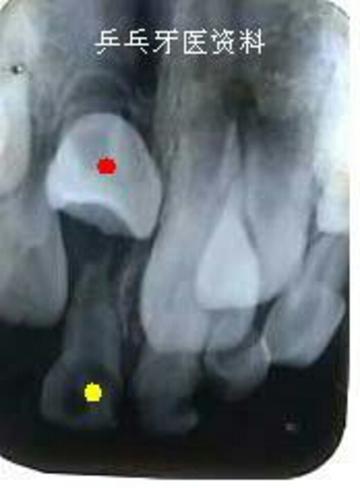

下面这2张图片显示一12岁患儿左下乳牙(黄点标记)根尖反复发炎导致对应恒牙(红点标记)水平阻生,不能正常萌出,后续经过一年时间的治疗才将这个恒牙牵引成功。

全景片示:左下乳牙牙根发炎导致恒牙不能萌出

牙片示:左下乳牙牙根发炎导致恒牙不能萌出